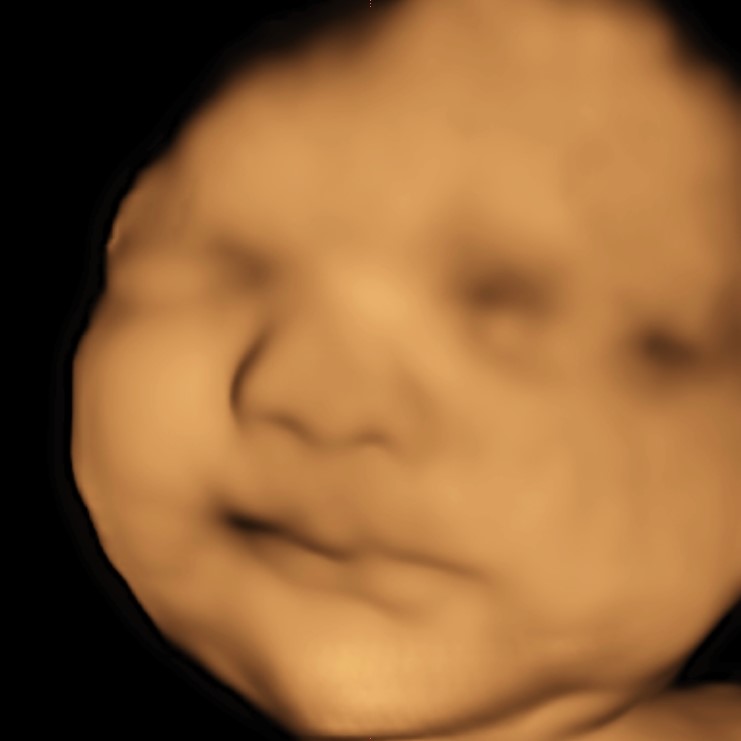

https://overthewombstudios.com/uncategorized/what-is-the-difference-between-3d-and-4d-ultrasound/3D muestra el tejido superficial del bebé, que se parece más a las imágenes reales. Podemos ver la redondez de la cara del bebé, la forma de la nariz y los contornos de los labios, solo por nombrar algunos. El color está mejorado por computadora para hacer que las imágenes sean más atractivas y no el color real del bebé.

4D es simplemente el movimiento en vivo de las imágenes 3D unidas. El sistema que utilizamos, GE Voluson E8, ecografía 4-d proporciona el movimiento en tiempo real más rápido y cercano de cualquier sistema de ultrasonido de la industria. ¡Elegimos lo mejor para ti!

HD o HD Live es la tecnología más nueva y más grande en los avances del ultrasonido. HD utiliza una fuente de luz virtual para generar vistas más realistas y definidas del bebé. Es una linterna digital virtual que agrega sombras y reflejos de luz para crear una imagen 3D más profunda y refinada con un realismo anatómico excepcional. * La luz es. no emitido realmente*